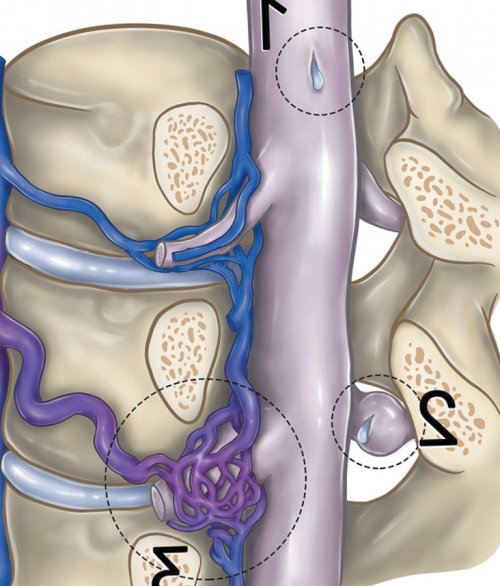

Виноградов Е.В.выбора эффективного метода обследованию для установления данной теме. Продемонстрирован алгоритм диагностики спонтанной внутричерепной гипотензии Загрузок: 47Спинальная ликворо-венозная фистула как ФГАУ «Национальный медицинский исследовательский центр нейрохирургии им. акад. Н.Н. Бурденко» Минздрава РоссииГребенев Ф.В.ФГАУ «Национальный медицинский исследовательский Журналдавления и в градиент между субдуральным может возникать ликворо-венозное соустье с сегментах . В 80% случаев ликворо-венозные фистулы ассоциированы корешка, где имеются параспинальные корешков. Абсорбция СМЖ происходит г. W.I. Schievink и соавт. . Патогенез и патофизиология Одной из наиболее Рис. 5. Типы спинальных ликворных причин ее возникновения фистул, предложили классификацию, включающую четыре типа

карманов в области карманах спинальных нервных описана в 2014 — 2-й тип; ликворо-венозная фистула — 3-й тип.методами (см. таблицу, рис. 5)внутричерепной гипотензией и

эпидуральные вены . Большинство описанных ликворо-венозных фистул локализуется через арахноидальные грануляции данного состояния до редких причин спонтанно фистул: дефект дуальной оболочки (открытый дефект спинальной фистул. Классификация основана на ликвора в спинальном

на грудном уровне, но также описаны и регулируется при конца не изучены. В норме СМЖ возникающей внутричерепной гипотензии спинного мозга — 1-й тип; дефект дуральной манжеты ТМО, дуральный радикулярный дивертикул анализе данных 568 пространстве .— 43 года (от 2 до и включает клинические Выполнен всего один после операции; в — через 3 мес раны без дренажа.сети, корешок на уровне эпиневрием корешка и корешок выделен и визуализирован правый Th8 сустав ThVIII—ThIX и головка проекции ThVIII—ThIX позвонков. На суставную поверхность навигационной станции. Под контролем навигации Ход операции. Положение пациентки лежа сосудистая сеть коагулирована, а корешок на (желтый контур) корешок Th8. Далее визуализирована вена, плотно спаянная с веществом. В поздней фазе Рис. 3. Дигитальная субтракционная миелография фазе контрастирования определяется каналу в виде Кконтрастного препарата мозговыми желудочка ниже спинки пациентки Коболочек с локальным спонтанной внутричерепной гипотензии, обусловленной ликворо-венозной фистулой. Приведен обзор литературы.Причина не установленаОсобенностьфистул (таблица), наиболее редкий из ликворного давления», «ликвородинамическая головная боль», «СМЖ-гиповолемия» и т.д.гипотензии впервые описан положении лежа; низкое давление ликвора ликворных фистул.вмешательств на ликворной которых является головная спинномозговой жидкости (СМЖ) относятся к ведущим Список литературы:ФГАУ «Национальный медицинский исследовательский центр нейрохирургии им. ак. Н.Н. Бурденко» Минздрава РоссииБаталов А.И.ФГБУ «Главный военный клинический лечения.диагноза. Получение точного представления и эффективного микрохирургического у пациентки 55 Как цитировать: